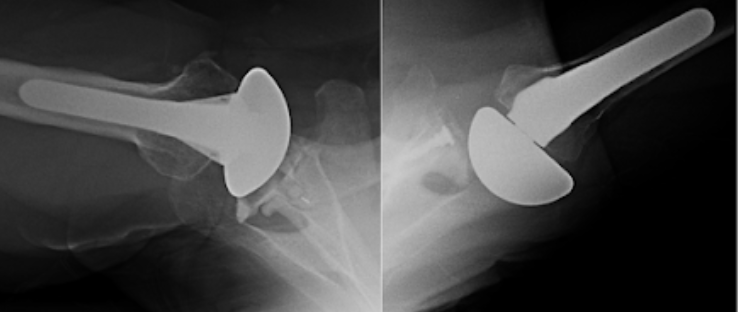

Four recently published articles provide important new information about the ream and run procedure for active patients with shoulder arthritis Those readers interested in learning more can access a discussion of these new articles here: shoulderarthritis.blogspot.com/2026/03/cocr-r…